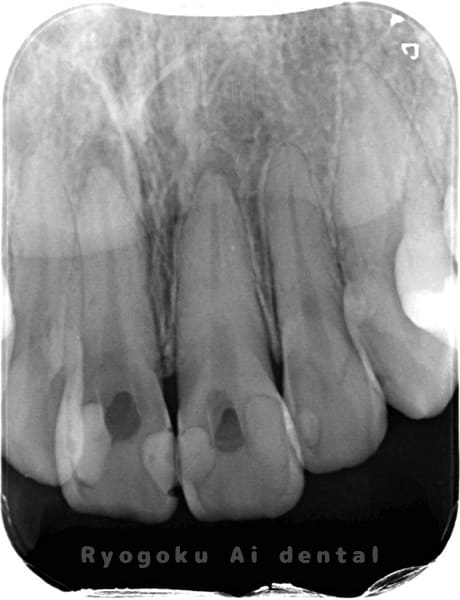

Case10

-

- 原因

- 失活歯

- 治療内容

- ブリーチング

- 治療費用

- 264,000円(2歯分、ダイレクトボンディング費用は含まない)

前歯の色が気になるとのことでご来院された患者様です。根管治療を行なった後、ブリーチングを行いました。今後、プラスチック部分の変色を治療する予定です。

<リスク・副作用>

治療中もしくは治療後に急に痛みが出る場合があります。感染が強い場合には痛みが激しいことがありますので、その際は痛み止め、抗生剤を処方する場合があります。

また、ダイレクトボンディングは強い衝撃などにより欠けたりすることがある。経年的に劣化(変色)してくる可能性がある。